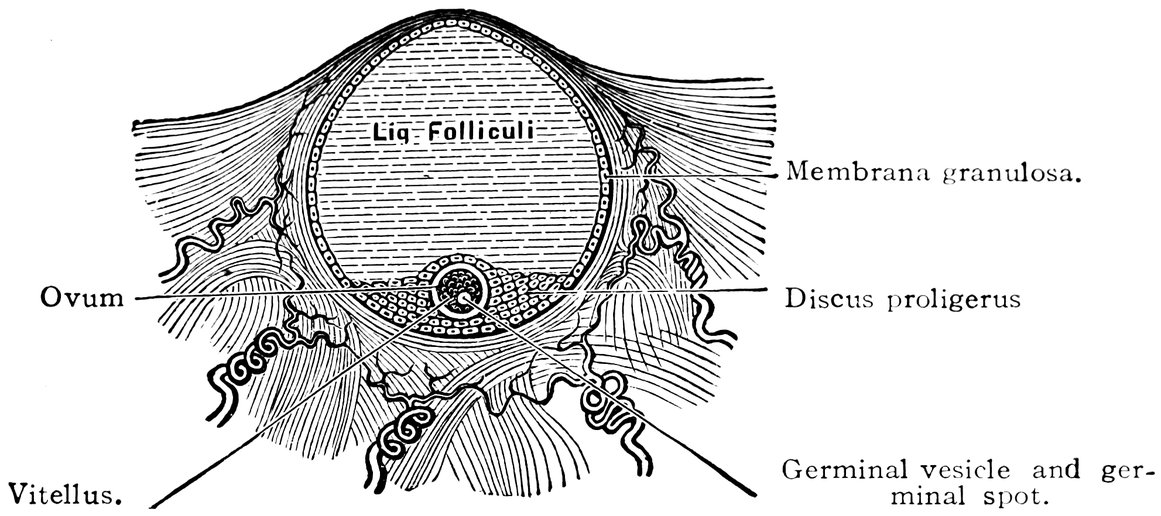

| 17. | Graafian follicles | 62 |

| 86. | Diagrammatic Representation of the Graafian Follicle | 585 |

We must first consider the changes in the ovaries, which play an etiologically important part. At the onset of puberty, the follicular masses of the ovary exhibit a more active growth, the follicles increase in size, with their contained ova they approach the surface, and finally, by the bursting of the follicles, the ova are extruded. Then, in the life-phase in which conception occurs, and under the influence of the hyperæmia of all the pelvic viscera that accompanies this process, a notable development of the corpus luteum takes place, this latter body reaching its maximum size in the eleventh week of pregnancy, subsequently undergoing involution and leading to the formation of a considerable scar. Finally, in the critical period of life in which the menstrual flow ceases, a continually increasing growth and new formation of connective tissue-stroma takes place in the ovaries at the expense of their cellular constituents, and a regressive metamorphosis of the graafian follicles occurs.